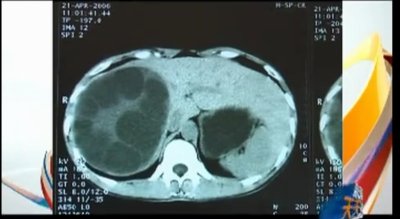

今回の事件に関しては、寄生虫やその卵の量から見て、女性が小さい頃によく食べていたカエルなどから寄生した可能性も指摘されている。しかしながら、中国では、屋台の肉が原因で、体内が寄生虫に支配されてしまう事件が非常に多いことも事実だ。

今年1月には雲南省に住む23歳の女性が、屋台で食べた肉が原因で、大脳から眼球、脚部に至るまで全身を寄生虫に侵されたとしてメディアでも大きく報じられた(華訊財経)。